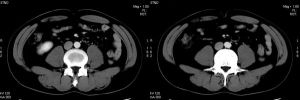

(4)CT 可發現患側腎體積明顯縮小。